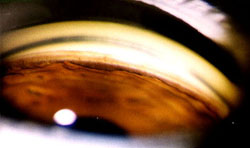

Oční tomografy HRT3 a SOCT jsou základními vyšetřeními při komplexním vyšetření. Přesto je velmi důležité vždy se také podívat Volkovou čočkou 60D nebo 90D v mydriáze na štěrbninové lampě a zhodnotit " vlastním pohledem" papilu a vrstvu nervových vláken /v zeleném světle/. Potom teprve popsat nálezy na tomografech.